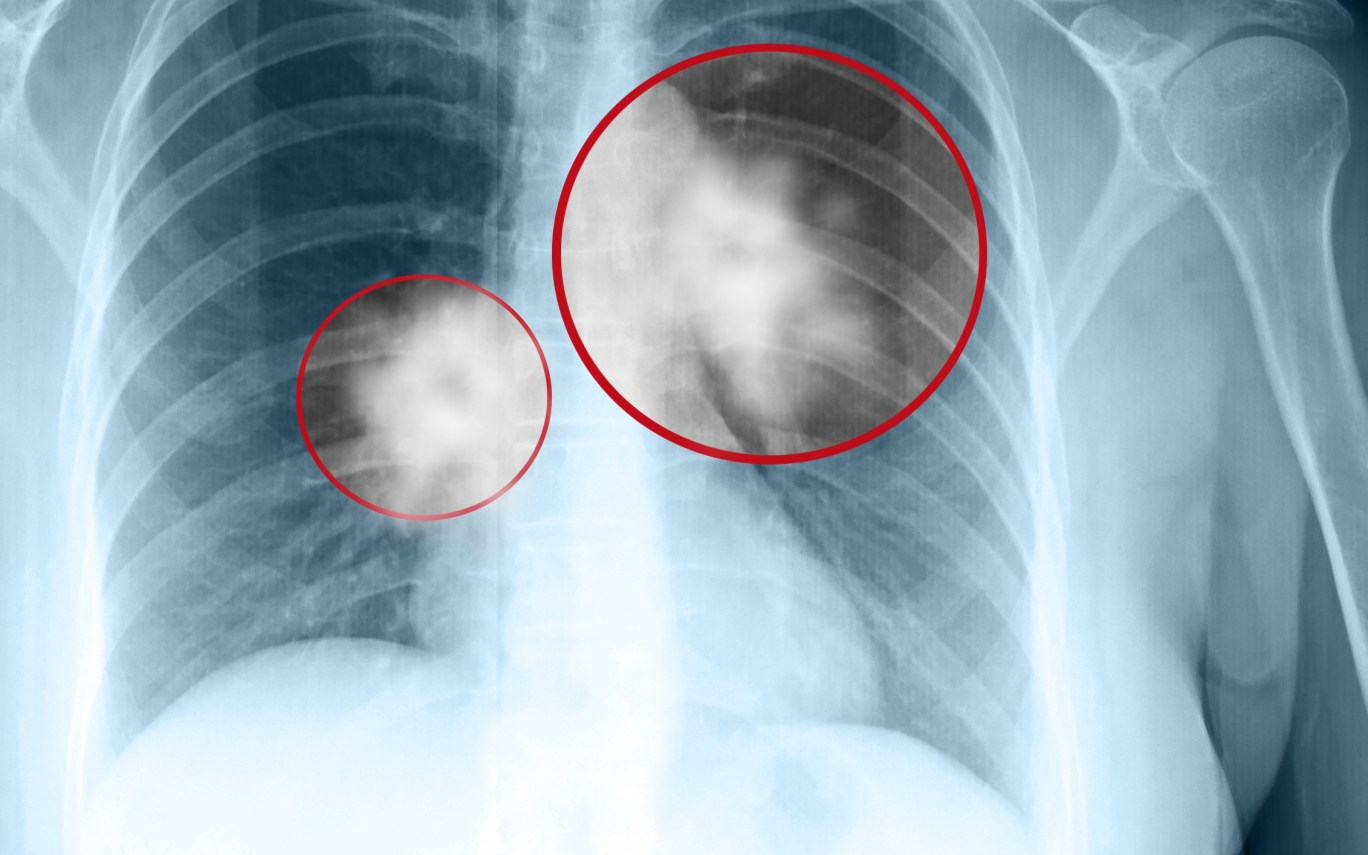

5. Ung thư phổi:

Theo thống kê từ Tổ chức Ung thư toàn cầu (GLOBOCAN), ung thư phổi là bệnh ung thư phổ biến đứng thứ 2 trên thế giới (chiếm 11,4%) với khoảng 2,2 triệu ca mắc mới năm 2020. Đây là căn bệnh có tỷ lệ tử vong cao nhất trong tất cả các bệnh ung thư với gần 1,8 triệu ca tử vong trong năm. Tại Việt Nam, GLOBOCAN ghi nhận có hơn 26.000 ca mắc ung thư phổi và gần 24.000 ca tử vong. Ung thư phổi được sàng lọc bằng chụp cắt lớp vi tính phổi liều thấp và được khuyến cáo sàng lọc đối với những đối tượng sau: Độ tuổi từ 55 – 74 tuổi có sức khỏe tốt, hút thuốc lá >= 30 gói/năm, đang hút thuốc lá hoặc đã bỏ thuốc trong vòng 15 năm vừa rồi.